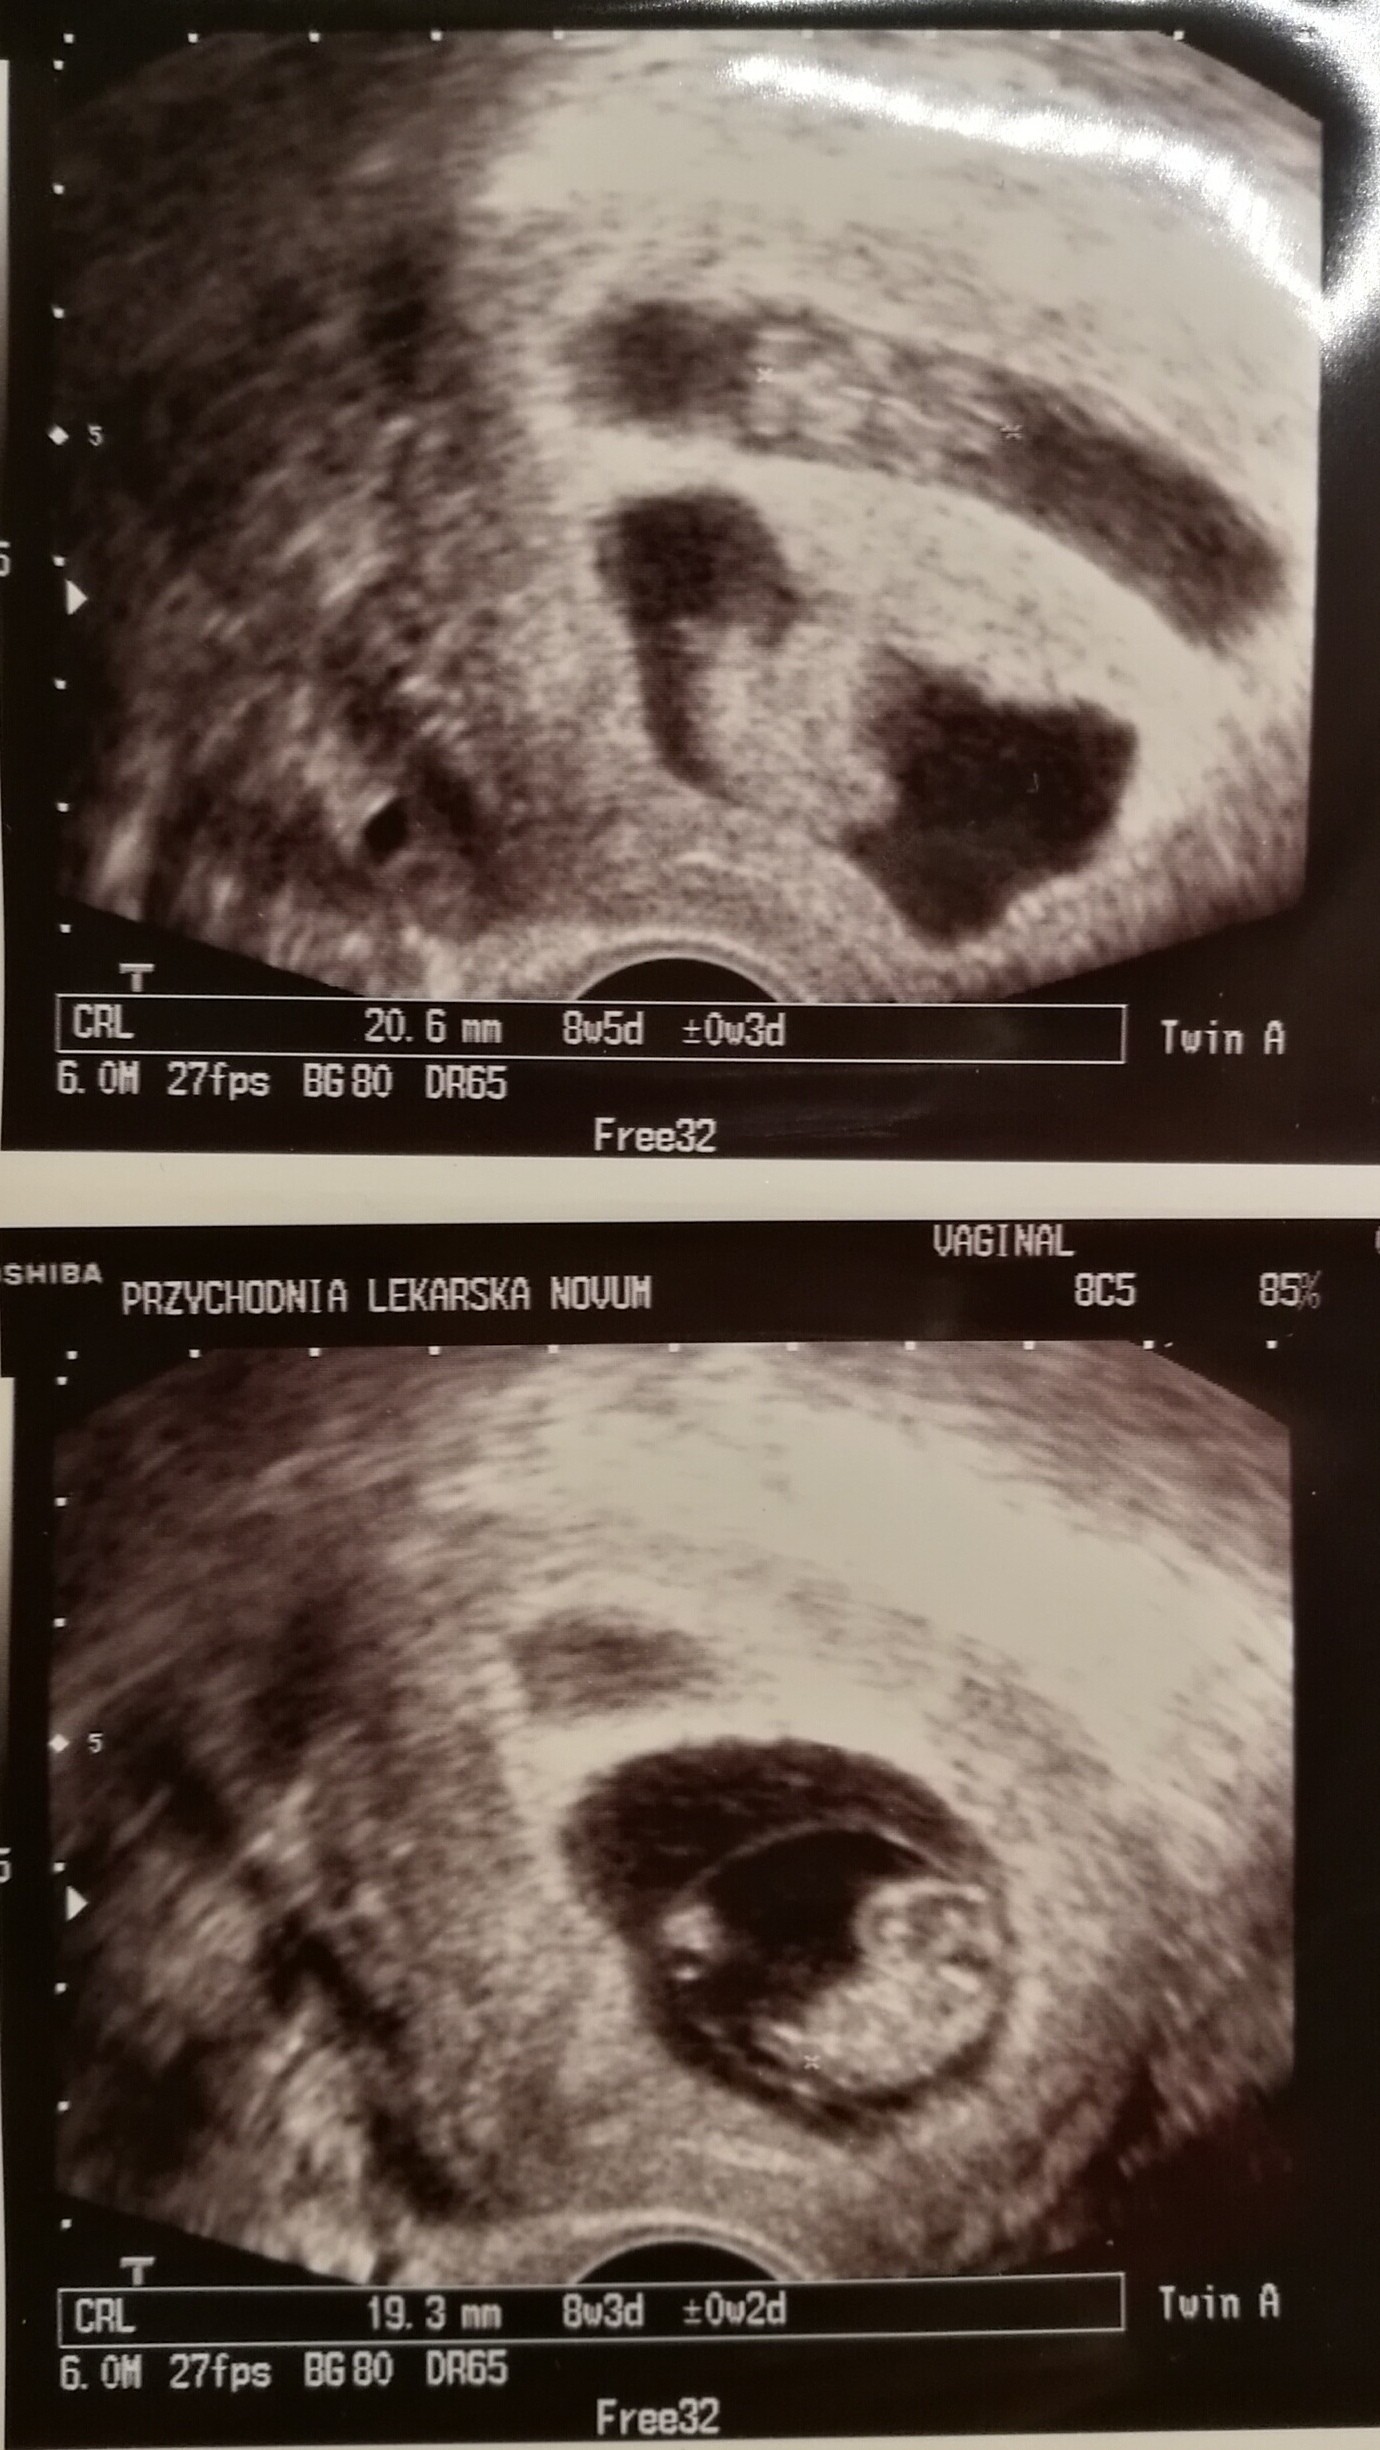

Udało się :-D moje Cudowności!

Załączniki

• IMG_20180104_173327.jpg

IMG_20180104_173327.jpg

489,5 KB · Wyświetleń: 142